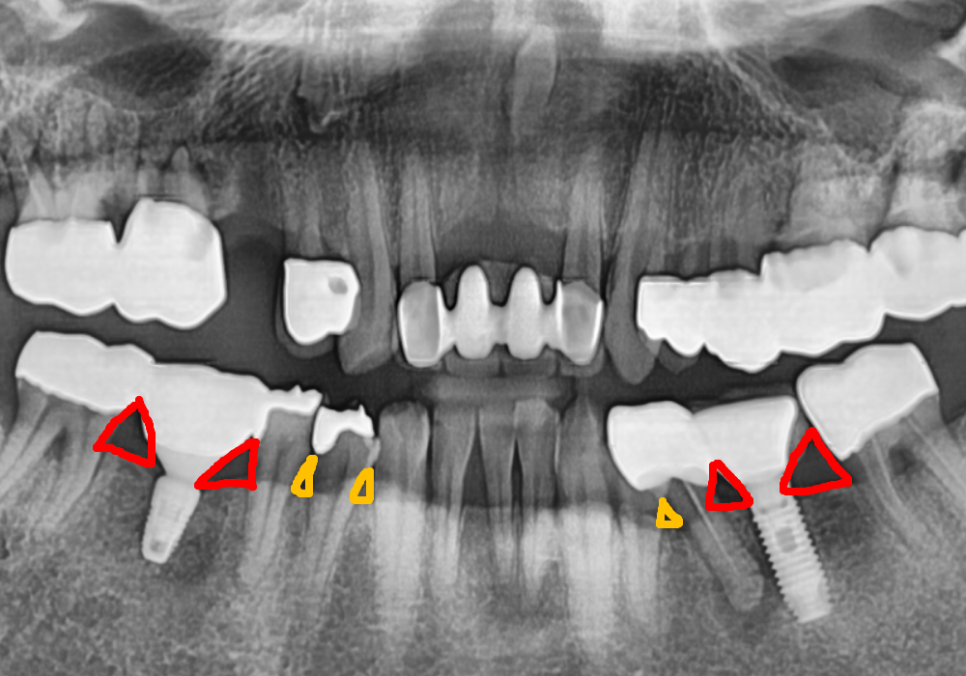

방사선 사진을 살펴보니,

자연치아 주변의 뼈가 까맣게 녹아내려 있었고,,

그 염증이 바로 옆 임플란트 주변 뼈까지

군데군데 녹이고 있는 상황이었습니다.

음식물이 지속적으로 끼고 관리되지 않으면서

염증으로 인해 잇몸뼈가 점점 녹은 상태...

흔들림이 너무 심한 자연치아는

안타깝지만 발치를 하기로 결정했습니다.